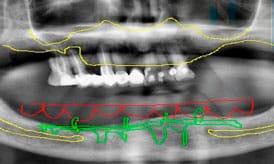

Fotos de implantes subperiósticos antes y después

Sabemos que conocer la experiencia de otros pacientes puede ayudarte a tomar la decisión de empezar tu tratamiento. Ver resultados reales ofrece una idea clara de cómo los implantes subperiósticos pueden transformar una sonrisa y la calidad de vida del paciente.

En este caso mostramos el antes y el después de un paciente con atrofia ósea severa y la rehabilitación conseguida gracias al tratamiento de implantes subperiósticos en Valencia:

Antes

Proceso

Después